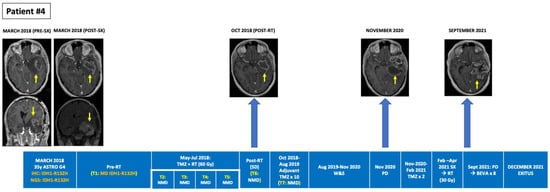

Figure 2.

Tumour evolution in BEAMing ctDNA-positive patient #4. A 66-year-old man diagnosed with a large right temporal IDH1-R132H mutant and MGMT methylated glioblastoma underwent a subtotal resection. After surgery concomitant RT + TMZ was administered. A single adjuvant TMZ cycle was administered after RT due to clinical deterioration, partly due to a non-obstructive hydrocephalus that required a ventriculo-peritoneal valve placement. Plasma ctDNA analysis pre- and post-RT revealed no IDH1 mutations. Eight months after RT, in February 2018, progressive disease occurred with appearance of L1-L2 leptomeningeal dissemination that was treated with palliative RT (5 × 4 Gy). BEAMing plasma ctDNA analysis prior to L1-L2 irradiation, detected the IDH1-R132H mutation (VAF 0.377%). The patient died in April 2018, 12 months after diagnosis. BEAMing: Beads, Emulsion, Amplification and Magnetics, BEVA: bevacizumab, ctDNA: circulating tumor DNA, GBM: glioblastoma, IDH1: isocitrate dehydrogenase type 1, IHC: immunohistochemistry, MGMT: O6-methylguanine–DNA methyltransferase, MUT: mutant, NGS: next-generation sequencing, NMD: no mutation detected, RT: radiotherapy, SX: surgery, TMZ: temozolomide, VAF: variant allele frequency, W&S: wait and see.